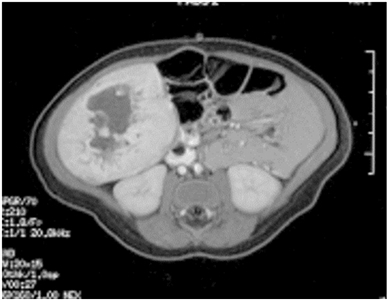

On MRI, vascular tumors of the liver are hyperintense on T2 imaging and hypointense on T1 imaging, with postcontrast imaging demonstrating early peripheral enhancement with eventual diffuse enhancement.[76] In practice, these tumors have been classified according to their clinical characteristics and radiological assessment.[76,154] In general, hepatic vascular tumors can be benign or malignant.